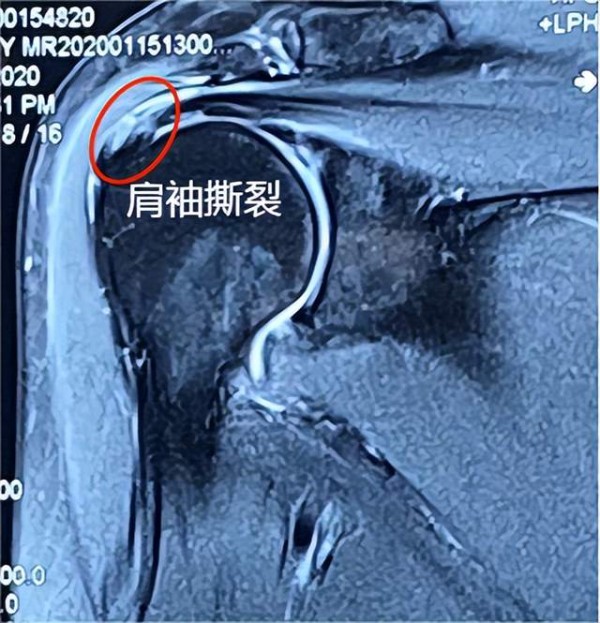

今天我们来了解一下肩关节疼痛的第一个原因----肩袖损伤。

肩袖是由冈上肌、冈下肌、肩胛下肌、小圆肌肌腱分布在肩关节前、后、上方包绕肩关节形成的袖套样的组织。

肩袖损伤后有哪些表现?

肩袖损伤后肌腱功能丧失或者减弱,导致肩关节活动受限,主要表现为上举无力,力量较对侧明显下降,在健侧手帮助下可以完成上举。还有一个典型表现是夜间疼痛。